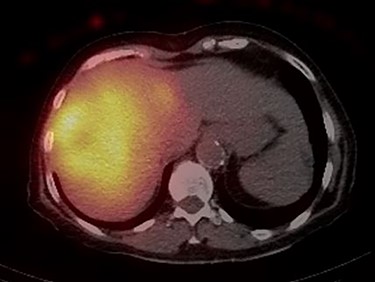

The consensus from the multidisciplinary liver tumor board was to proceed with Y-90 TARE to achieve tumor shrinkage and to induce left liver lobe hypertrophy in preparation for surgical resection. In February 2019, the patient underwent a Y-90 TARE, and a dose of 2.71 GBq (73.4 mCi) of glass microspheres (TheraSpheres, Boston Medical) was injected into the right hepatic artery (Fig. 3). The delivery of the dose was verified using Bremsstrahlung liver SPECT imaging post-injection (Fig. 4). Based on this activity distribution, the dose was calculated on a voxel-by-voxel basis using Sure Plan software (MIM, Cleveland Ohio). The local deposition method (LDM) was used, and the dose was scaled by the amount of activity injected.

Post-Y-90 Bremsstrahlung SPECT/CT demonstrates uptake predominantly within the main right liver lobe lesion (GTV) with minor uptake into the Segment IVA lesion.

Post-treatment dosimetry done using the Bremsstrahlung liver SPECT image and the Sure Plan software demonstrated that the mean dose delivered to the main right liver lobe tumor (GTV) was 156 Gy. Ninety-five percent of the GTV received 108 Gy with a max dose of 213 Gy. The mean dose to the Segment IVA lesion was only 62 Gy, with 95% of the lesion receiving 36 Gy (Figs 8 and 9).